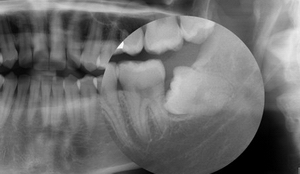

impaktirani umnjaci, operacija umnjaka

Hirusko vadjenje impaktiranih umnjaka

Vađenje impaktiranog umnjaka je hiruška procedura i bitno se razlikuje od vađenja izniklih zuba. Postoperativne komplikacije su moguće. Da bi se izbegle, potrebno je...